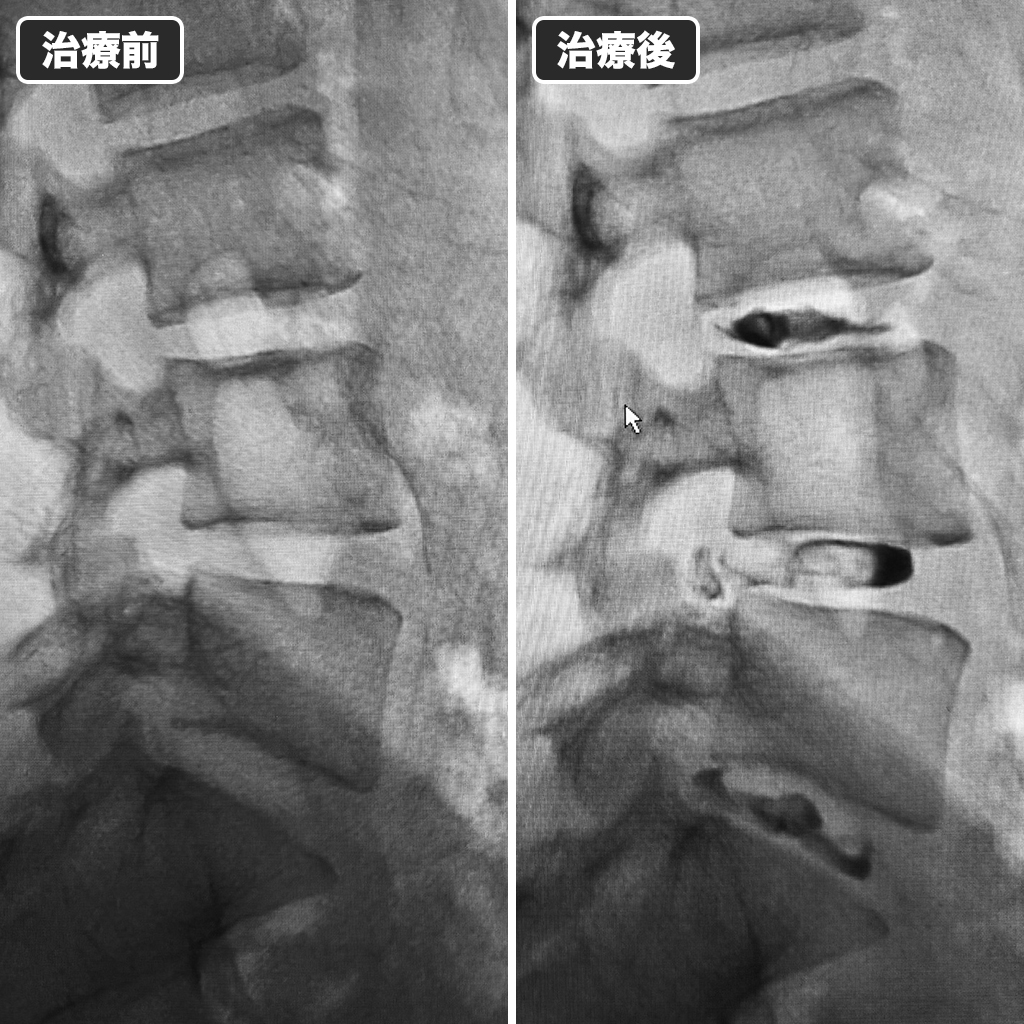

治療前後のレントゲン写真

治療前後のレントゲン写真になります、左側が治療前、右側が治療後になります。治療時間は14分ほどでした。鎮静剤を併用したために痛みや不安を感じられることはありませんでした。